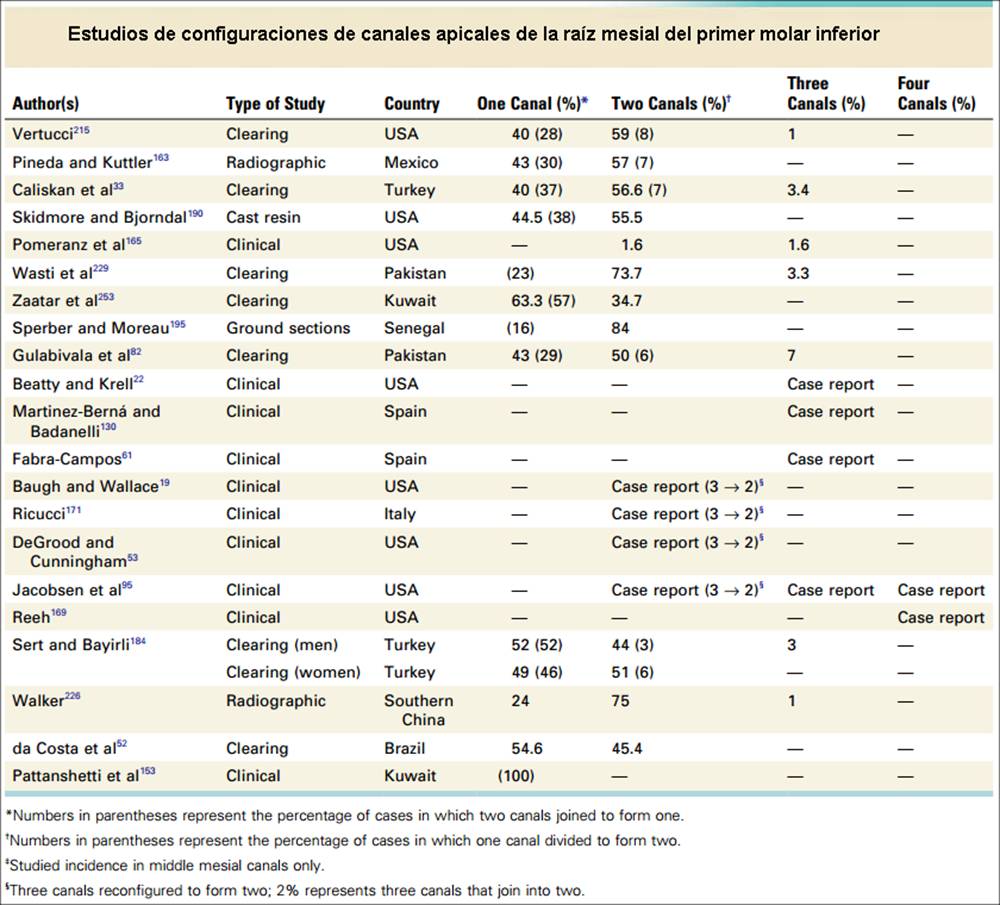

Primer Molar Inferior Esta pieza dentaria es la más voluminosa de la arcada. Posee por general dos raíces bien definidas una mesial y otra distal, ambas aplanadas en sentido mesiodistal. La raíz mesial presenta una curvatura acentuada, mientras que la distal puede ser algo curva o recta. Cuando tiene tres conductos el mas amplio es el distal con una sección oval y su curvatura es suave o recta. Si presenta cuatro conductos la raíz distal contendrá dos de ellos y son de diámetro más pequeño y en caso de presentar dos conductos, ambos son amplios. Segundo Molar Inferior Es de menores proporciones que el primer molar y sus raíces en general son dos y diferenciadas como en el primer molar ,así como también pueden presentarse fusionadas parcial o totalmente. |